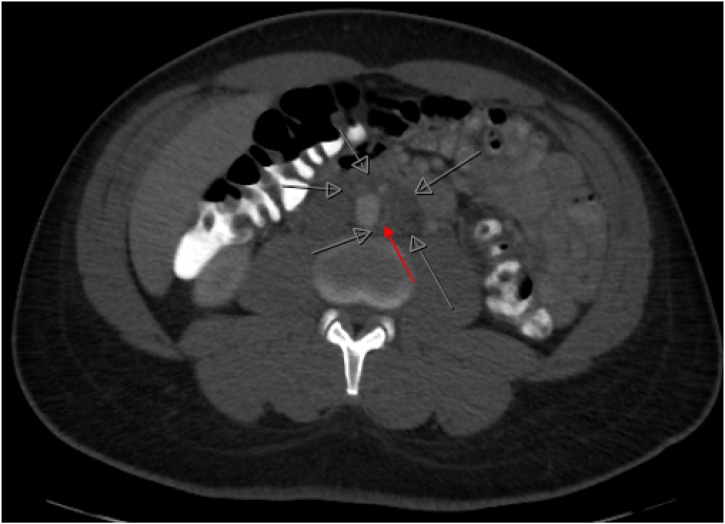

A 36-year-old man with well controlled HIV, on abacavir-lamivudine-dolutegravir (CD4 count of 931 cells/μL with undetectable viral load), presented with a one-week history of lower abdominal pain radiating to his back. He initially attributed the pain to constipation but when the pain progressed, he decided to seek medical advice at a local emergency room. CT scan of the abdomen and pelvis with oral and intravenous contrast showed an ill-defined infrarenal periaortic mass with an adjacent eccentric thrombus in the abdominal aorta and subtle enhancement of the vasa vasorum concerning for focal aortitis (Fig. 1). Initial concern was for a neoplastic process and outpatient CT guided biopsy was scheduled, but symptoms intensified over ten days prompting further medical evaluation. CT angiogram of the chest and abdomen showed a pseudoaneurysm of the aorta (Fig. 2A) and a focal dissection extending to the aortic bifurcation (Fig. 2B). Given these findings, the patient was transferred to our tertiary care center for further surgical and medical management.

Fig. 1.

Axial view of CT abdomen and pelvis with oral and intravenous contrast. Red arrow indicates thrombus and early dissection with focal aortitis. Open grey arrows show ill-defined soft tissue abnormality surrounding the infrarenal aorta, measuring 4.3cm × 4.2cm. (For interpretation of the references to colour in this Figure legend, the reader is referred to the web version of this article).

C. fetus aortitis characteristically has rapid progression to aneurysm formation and subsequently, to aortic rupture. Overall mortality of C. fetus aortitis is 20–30 % but mortality approaches 100 % if rupture occurs before surgical intervention can be conducted [[10], [11], [12]]. Our case illustrates the rapid progression of C. fetus from focal aortitis (Fig. 1) to the development of pseudoaneurysm over ten days (Fig. 2). Once the pseudoaneurysm was identified, emergent open resection and neo-aortoiliac replacement with his left femoral vein was conducted. This case reinforces the need for a high index of suspicion to identify and surgically treat C. fetus aortitis, thereby preventing progression to aortic rupture and reducing mortality.